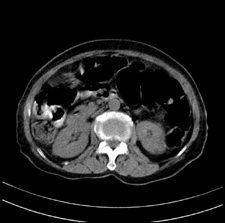

患者,女,75岁。腹痛,体黄5日,膝胸位时腹痛缓解。肝功能明日出来。彩超提示胆总管占位,未见血流信号。心电图提示s-t段改变。患者体质较弱,未能增强。

胆总管结石

胆总管多发结石

胆总管多发结石伴肝内外胆管轻度扩张。

胆总管上段,腔内有软组织密度影 ,ct值36-44hu。大家看有没有胆管癌的可能。

典型胆总管多发结石;增强扫描前后ct值是否发生改变是鉴别结石与占位的依据。